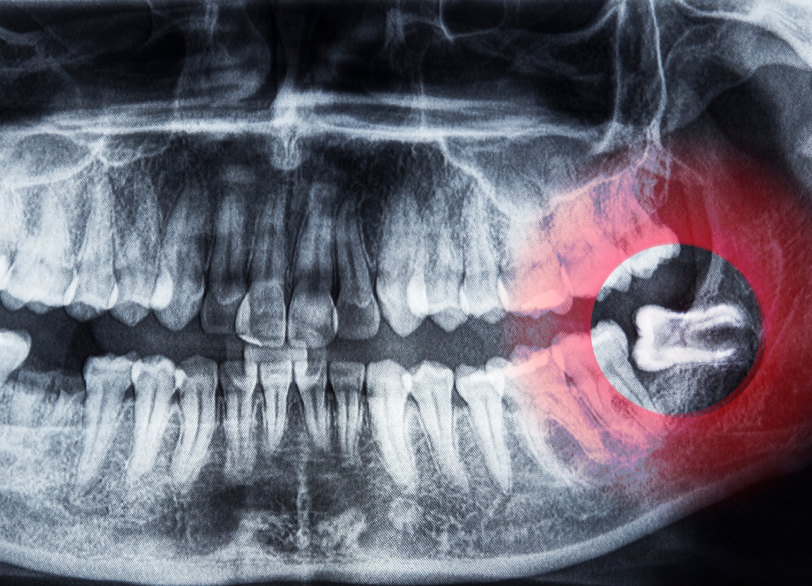

当院では、通常の二次元的なレントゲン撮影に加えて必要不可欠と判断した症例においては、必ず「歯科用CT」による撮影を行います。

歯科用CTを用いることで次のような情報を、ミリ単位で正確に把握することができます。

- 親知らずの根の形や本数、湾曲の度合い

- 顎の骨の中での親知らずの正確な位置と傾き

- 親知らずの根の先端と下歯槽神経との三次元的な位置関係

CTによる事前の詳細なシミュレーションは、手術中の偶発的な事故(神経の損傷など)のリスクを限りなくゼロに近づけより安全で確実な抜歯を可能にするための、いわば「手術の設計図」となる極めて重要なプロセスです。